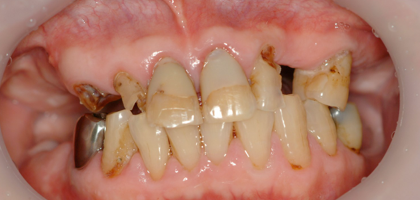

一日も歯がないという状態はありません。 この写真の方も前歯しか残っていませんが、インプラント手術当日まで前歯は残しておいて、その当日に抜歯、インプラントを入れて仮歯を固定しています。つまり、歯は一日で入るので、歯が無い、見た目が悪いという状態は全くありませんので、ご心配なく。大分県大分市スマイルライン歯科ではオールオンフォー(all- on- 4)の治療を全国でもいち早く行い数多くの症例を手掛けてきました。そして治療を行ったすべての患者様に喜んで頂いておりますのでご希望の方はまず、CTレントゲンなどで骨の形を診査しますのでお問い合わせください。

先日行ったall on 4の症例の写真です

前歯しかない患者様で前歯がないと見た目が困るということでお越しになりました